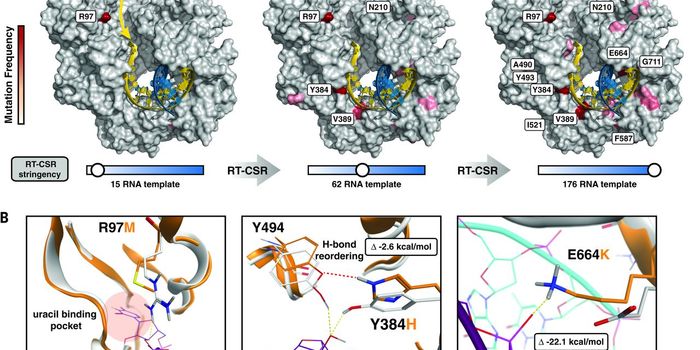

SEP 20, 2021Genetics & GenomicsHuman immunodeficiency virus (HIV) is a retrovirus, which is a type of virus that can write its genetic material into th ...